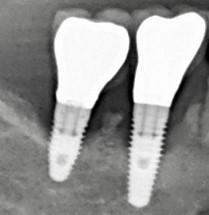

➜ la situation osseuse « PA » (Peri-implantitis Apparearance) comprend 5 classes PA0 à PA4 (fig. 3 à 6). établies selon les critères suivants: le nombre d’implants adjacents atteints (un seul implant, deux implants, ou au moins trois implants atteints), l’importance de la perte osseuse (selon le pourcentage de la hauteur d’implant qui a perdu de l’os : < 60 % ou > 60 %), le nombre de parois osseuses restantes autour du défaut (aucune, ou au moins une paroi).

Figure 3: exemple de péri-implantite PA1b ( Perte osseuse < 60 % de la hauteur implantaire, défaut de 1 à 4 parois avec cratère < 3 mm)

Figure 6 : exemple de péri-implantite PA 4b (perte osseuse < 50 % de la hauteur implantaire, avec ou sans cratère, défaut de 1 à 4 parois)